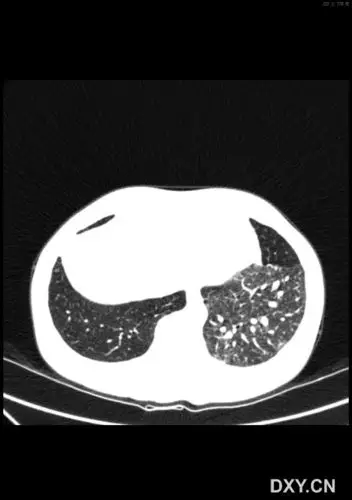

年轻女子咳嗽,咳痰2年,病因不寻常……_肺隔离症_医脉通

【影像读片】肺隔离症?